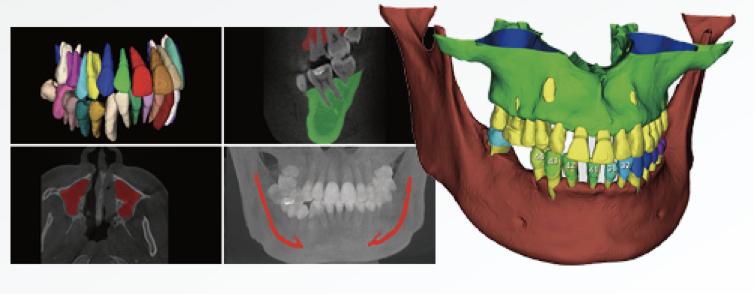

Exportação com um clique das principais estruturas anatómicas dentárias

Segmentação Inteligente Automática;

Extração Rápida de Informação sobre a Posição Dentária